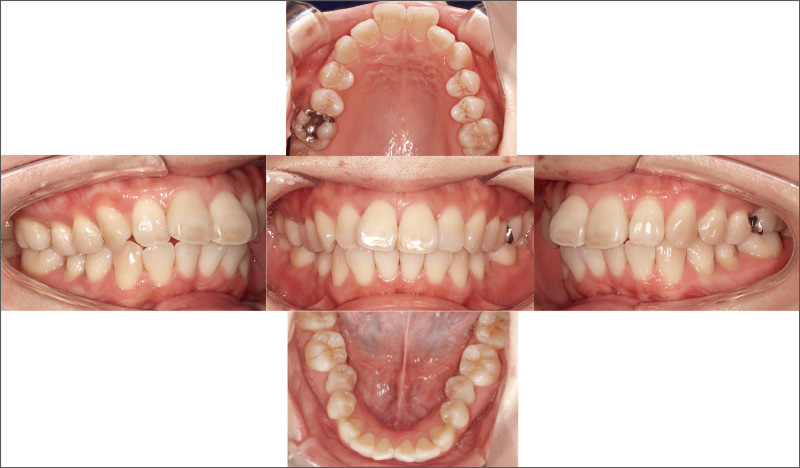

症例2-1 ₂の形態異常を主訴に来院した30代女性。審美回復には矯正治療が必要と説明したが、全顎的な矯正は希望されなかった。半年以内に終了する「iGo」による部分矯正治療には同意が得られたため、₁抜歯後に治療を開始した。 -

![[写真] 20週という短期間で歯列不正を改善](/academic/dentalmagazine/wp-content/uploads/sites/2/2025/09/194-5_photo08.jpg)

症例2-2 20週という短期間で歯列不正を改善。「クリンチェック治療計画」を再現性高く実行できた。「iGo」は矯正の範囲などに制約はあるが、歯牙移動について非常に再現性が高いことがわかる。 -